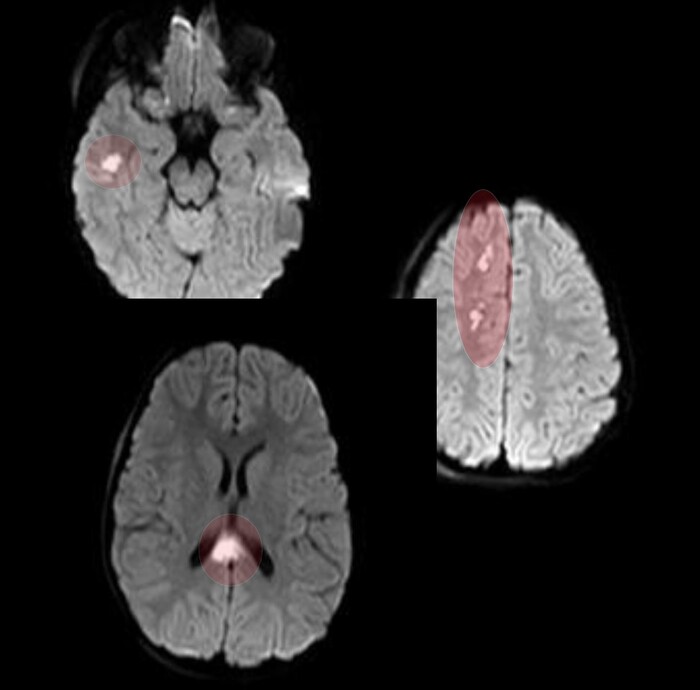

Очаги показывали также ограниченную диффузию на DWI-изображениях: